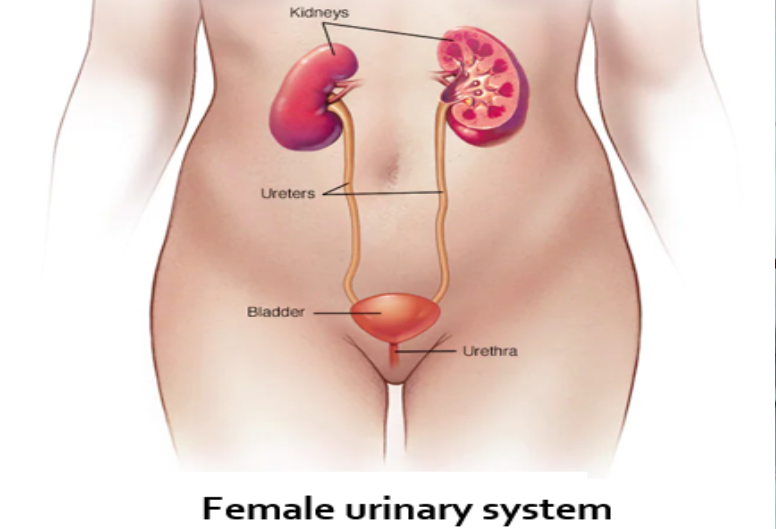

Dr Sushrut Fuladi is a well-known Consultant Nephrologist and Renal Transplant Physician with

expertise in treating patients of Acute Kidney Injury, Chronic Kidney Disease, Hypertension and

Diabetes related renal disorders, and renal replacement therapies.